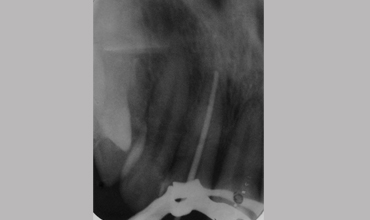

Management Of Fractured Tooth With Cast Post & Core